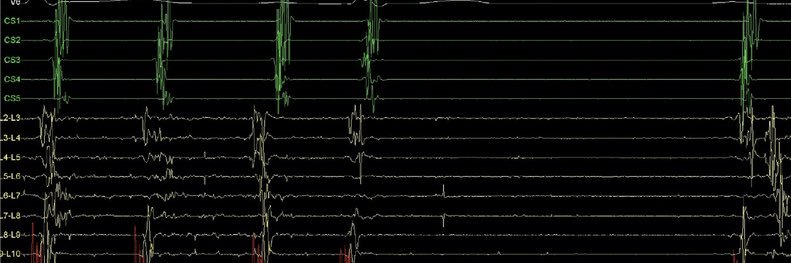

What exactly is #AFib burden? 🤔 It’s a term widely used in arrhythmia research—but still without a unified definition. #AFib burden can describe: ▪ symptoms during AF ▪ clinical consequences (stroke, HF) ▪ socio-economic impact ▪ or most commonly today — the proportion of time a patient spends in AF Continuous monitoring (CIEDs, wearables) is reshaping how we measure AF burden and revealing that not all AF is the same. Two patients may have identical AF burden but different patterns: 🎵 “Legato” – few long episodes 🎶 “Staccato” – many short episodes Understanding these differences may be key for risk prediction and treatment decisions. 🔖 More on this in #EHRA_ESC Consensus Document of #AFib burden bit.ly/40bOzKg #EHRAtopicweek